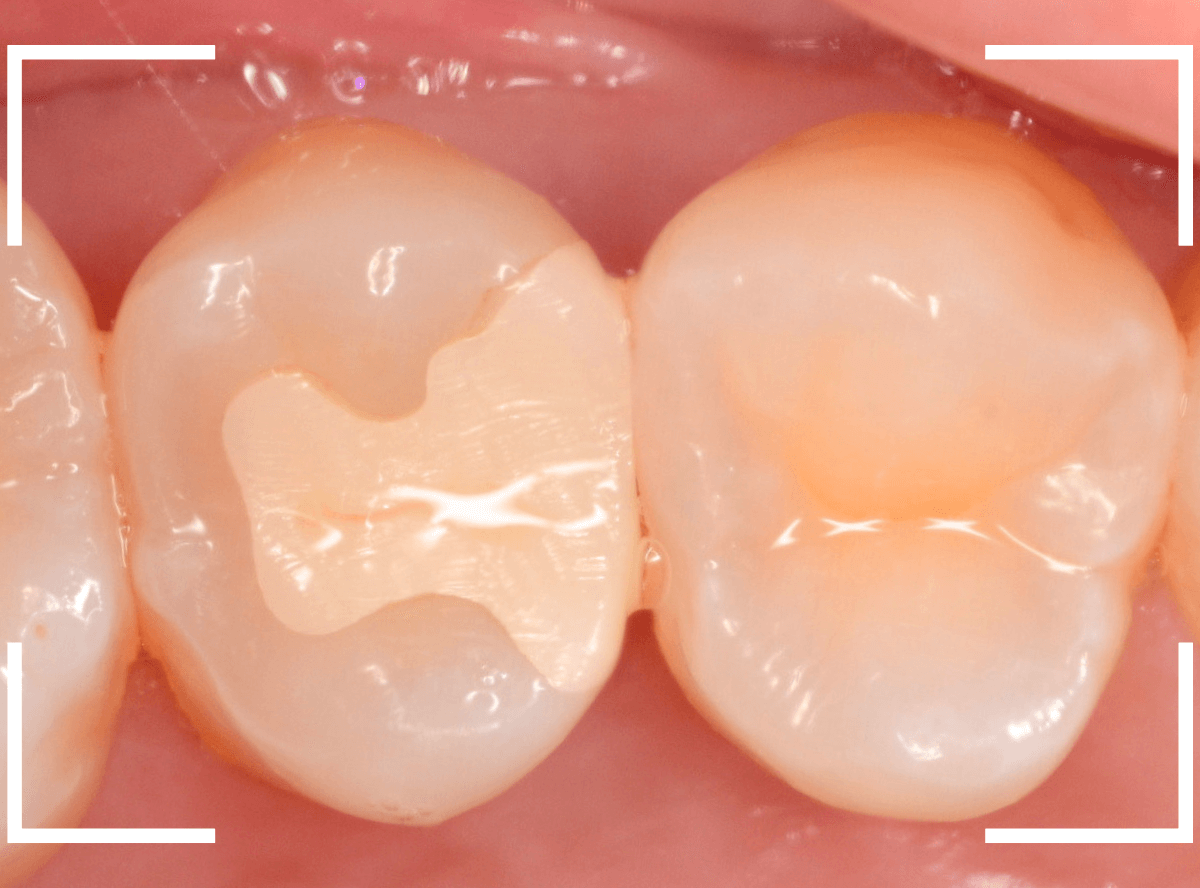

Case.26 4歯連続したセラミック・インレー

4本連続して歯と歯の間の虫歯を治療した患者さんのケースです。

虫歯を再発させないためには、歯と歯のすき間を物がつまらないよう、精密に再製する必要があります。

患者さんのご希望により、セラミック・インレーで修復する事になりました。

模型上で歯と歯のすき間を精密に再現・調整できるのが、セラミック・インレーの大きな利点です。

最終setした状態です。

左側の大臼歯2本が、ジルコニア・インレー

右側の小臼歯2本が、E-MAX・インレー

になります。

見た目にほとんど遜色ない仕上がりにできました。

普段あまりしない、4歯連続のインレー治療でしたが、精密に仕上げ・setする事が出来てホッとしました。